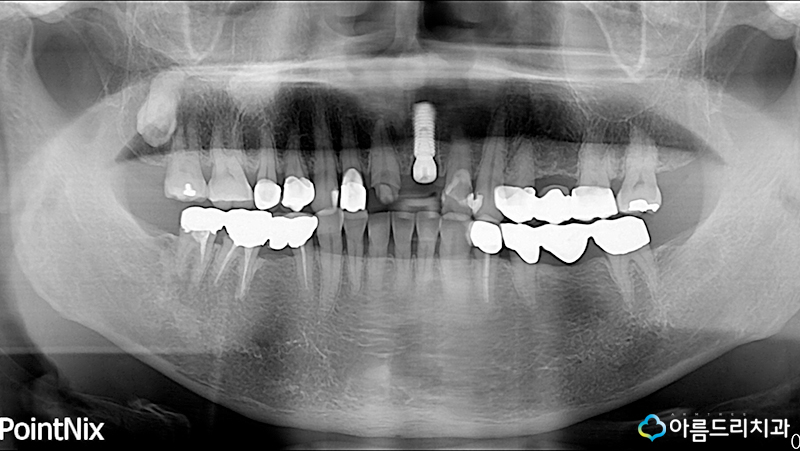

환자분께서 걱정하고 계시는 심미성을 고려한 전치부 앞니 임플란트에 대해 정확하게 설명을 드렸으며 환자분께서는 앞서 설명해드린 지르 코니아어버트먼트를 진행하기로 했습니다.

그리고 어떻게든 치아를 살리기 위해 노력 하는 아름드리는 치아탈구 옆에 깨진 11번 치아는 신경치료 후 크라운으로 치료했습니다.

그렇다면 과연 체결된 모습이 어떤지 궁금해하는 분들이 많으실텐데요.

바로 위의 사진이 지르코니아어버트먼트 의 체결된 모습인데 치아의 색상과 동일하기 때문에 위에 크라운을 씌우면 전혀 치아가 비쳐진 색이 어두워보이지 않습니다.

또한 아름드리치과는 다른 치아와의 어울림 즉, 자연스러움을 중요하게 생각하기 때문에 치아의 톤도 매우 신경쓴 결과물이 나옵니다.